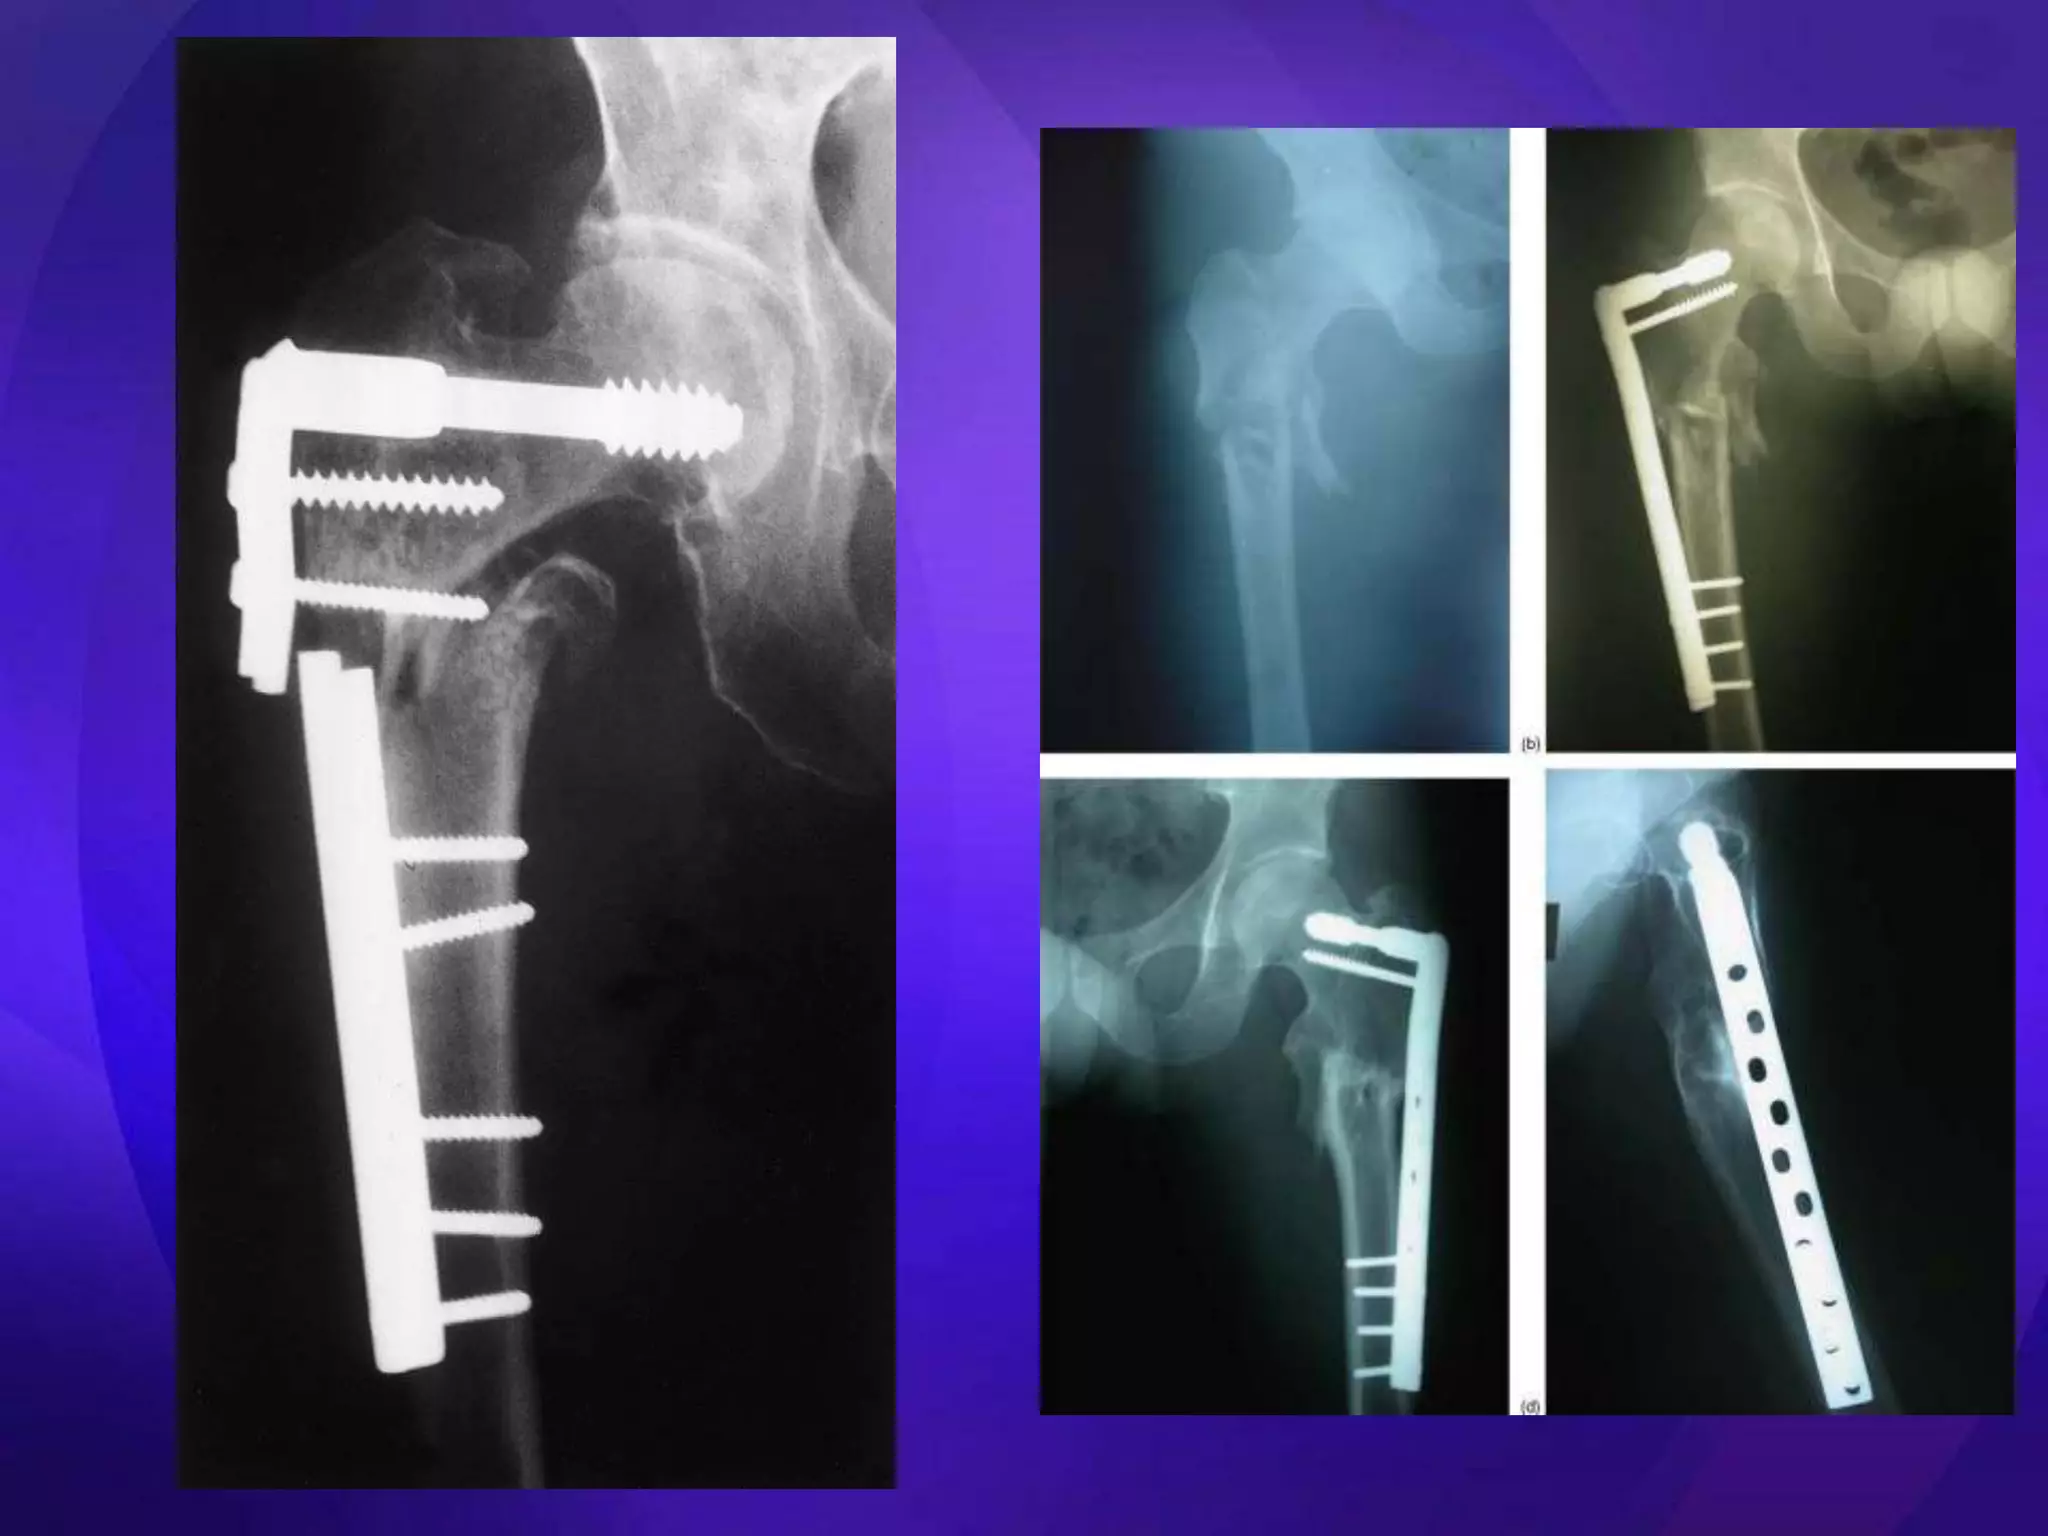

• Key issues – Medial cortical buttress – Reduction (esp varus deformity) • Extramedullary – ORIF – DHS, Medoff Sliding Plate, DCS, blade plate, locking plates • Intramedullary – Centromedullary – Cephalomedullary – Short vs long

• Easier toinsert than blade plate • Plate/ screw breakage • 20-30% failure – Elderly – Unstable #s – Early weight bearing • Nonunions

• Designed for intertrochanteric #s • Easier to insert • Entry point may be # • 25% failure – Loss of fixation • ? Should be avoided

• Infection • VTE •Implant failure – Varus malreduction – Screw placement in femoral head • Malunion – Shortening – Rotational deformity – Varus • Nonunion ( 0-8%) – Significant pain >6 months with the inability to FWB – Stable fixation - autogenous bone grafting – Exchange nailing with over-reaming